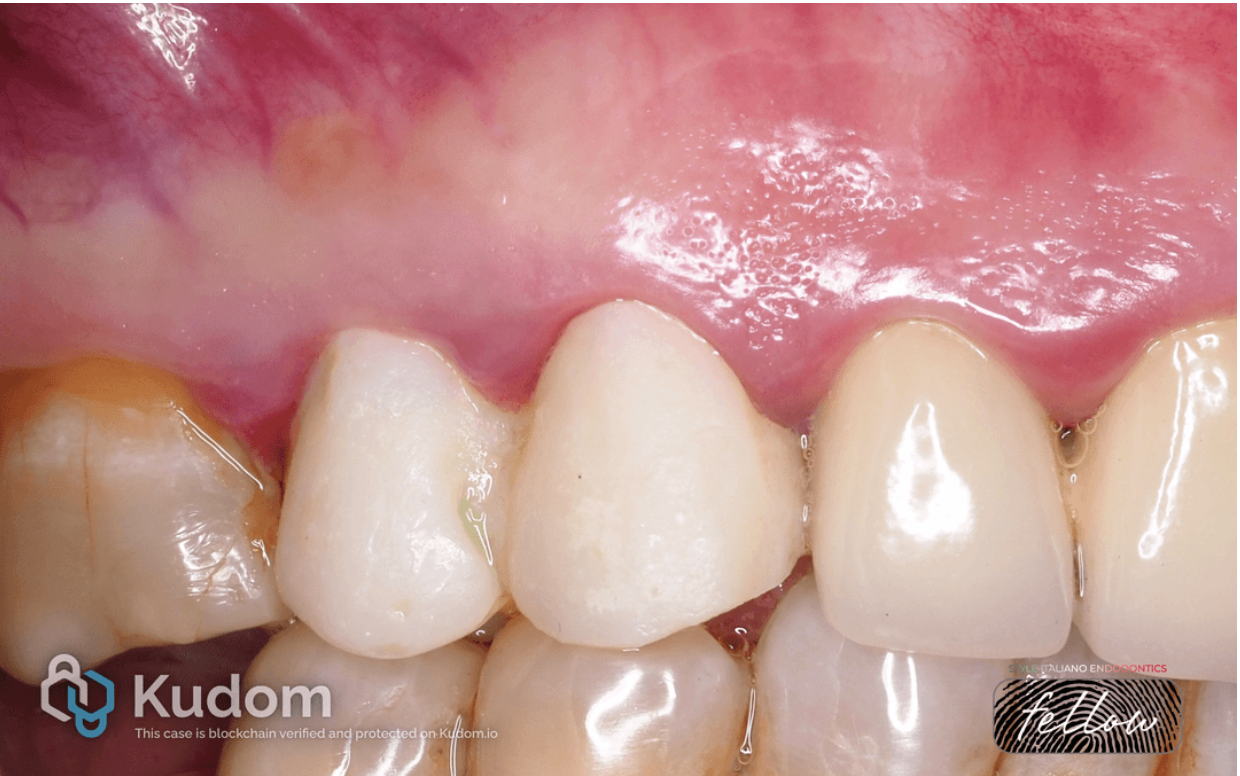

Fig. 1

In 2018, a patient (female) presented with complaints of pain upon pressing on the tooth, a sensation of fullness in the gum, serous fluid discharge from a fistula, and bad breath